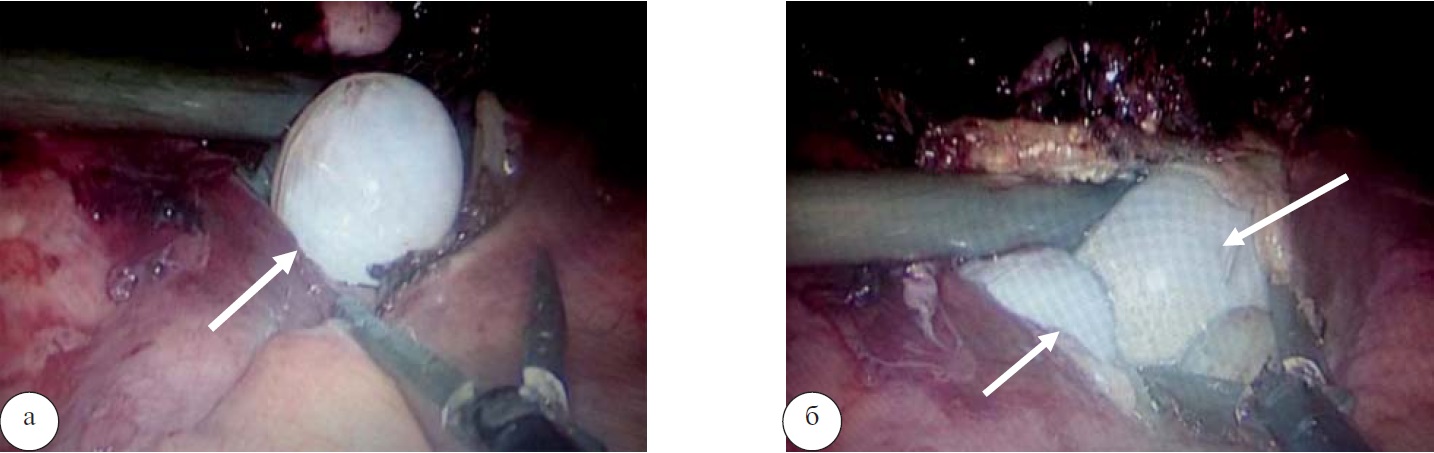

Произведена мобилизация печени путем рассечения серповидной связки. Установлена возможность выполнения эндовидеохирургической перицистэктомии. Выполнена пункция образования – удален жидкостный компонент кистозного содержимого, в полость введен раствор бетадина на 15 мин. В полости кисты определялись множественные сколексы диаметром от 1 до 2 см (рис. 5).

Рис. 5. Эхинококковые сколексы после вскрытия капсулы кисты

Образования удалены без вскрытия их капсул с помощью электроотсасывателя хирургического с увеличенным по толщине наконечником. Общий объем удаленных кист составил около 1200 мл. С целью ликвидации остаточной полости произведена атипичная резекция 4, 7 и 8 сегментов печени с обработкой зоны резекции аргон-плазменной коагуляцией. В область резекции установлен дренаж. Дебет отделяемого по дренажу за сутки составлял около 100 мл серозносукровичного отделяемого. Выполнялась контрольная фистулография. Связи полости с протоковой системой печени не выявлено.